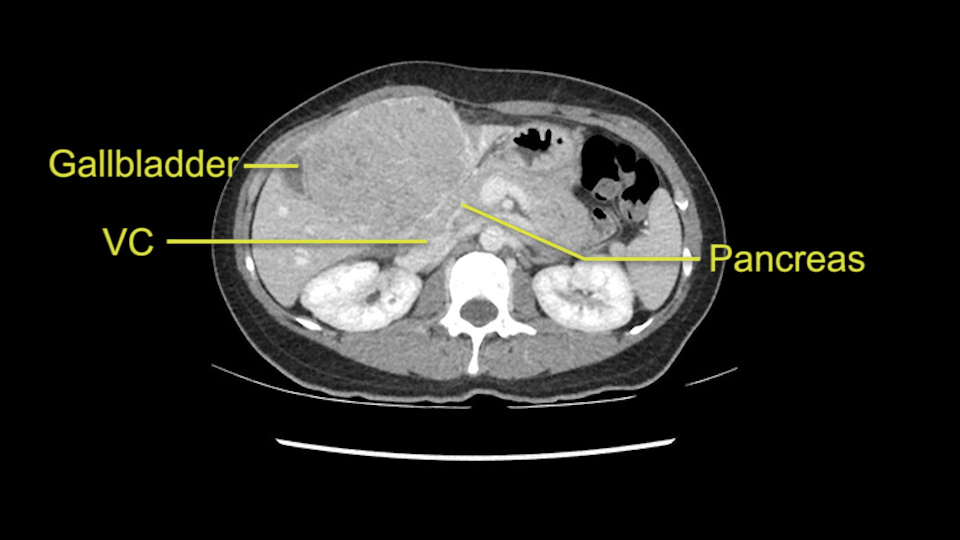

When you see the axial sections of the scan, you find it's a largely exophytic mass and its well-encapsulated. So this is typically true of a well-differentiated hepatocellular carcinoma. If you look at this, this is the gallbladder which is being displaced to the right and the mass is in the Sg4 of the liver, exophytic, projecting down. As it is coming down, it is also displacing the duodenum and the head of the pancreas which is being pushed towards the left and it's going right up to the cava, the start of the anterior surface of the cava. Obviously getting a lot of collaterals and vascularity from all the vessels around but one has to be very careful in evaluation of the main portal pedicle in this particular case and of course arterial inflow to the Sg4 and of course the left lobe of the liver.

Now let’s look at some specific anatomical points for planning this surgery. First thing you see when you see a left hemihepatectomy is that where is the left portal vein and the right portal vein branching? And what is the stump of the left portal vein available for you for ligation? In this particular case, you’ll find that there’s overhanging of the tumor but left portal vein pedicle is sufficiently available for us for ligation.

Now coming to the duodenum, we can see that the stomach is coming down, and as it comes down to the head of the pancreas, it’s compressed by the mass which is distorting the duodenum completely. Is there invasion of the duodenum or not? When you see a little above, there is a very well nicely capsulated tumor so my impression is that it is only displacing the duodenum, may not be invading the duodenum. But however intraoperatively one has to be careful in dissecting the duodenum from the tumor.

So in planning for this operation, as I look at the scans, I first visualize the arterial phase and I can see that there’s are a lot of big feeding arteries to this large tumor. Likely all the right side vessels feeding the right side of the liver: right hepatic artery and likely the Segment 4 artery are spared from the tumor. It’s likely the left hepatic artery is ramificating and giving feeding arteries to this tumor. It certainly looks like a large mass that its compressing other structures like the cava, the pancreas, the stomach; but I think there’s a plane and we can see that better in the venous phase. There’s a plane of separation between the gallbladder, the pancreas, the cava, that this tumor is abrupting but likely not invading. Usually, these masses actually don’t invade at that level and basically are pushing the tissues and once you open, you’re able to separate the tumor. Sometimes there’s some adhesions but you can actually separate and there’s usually no invasion.